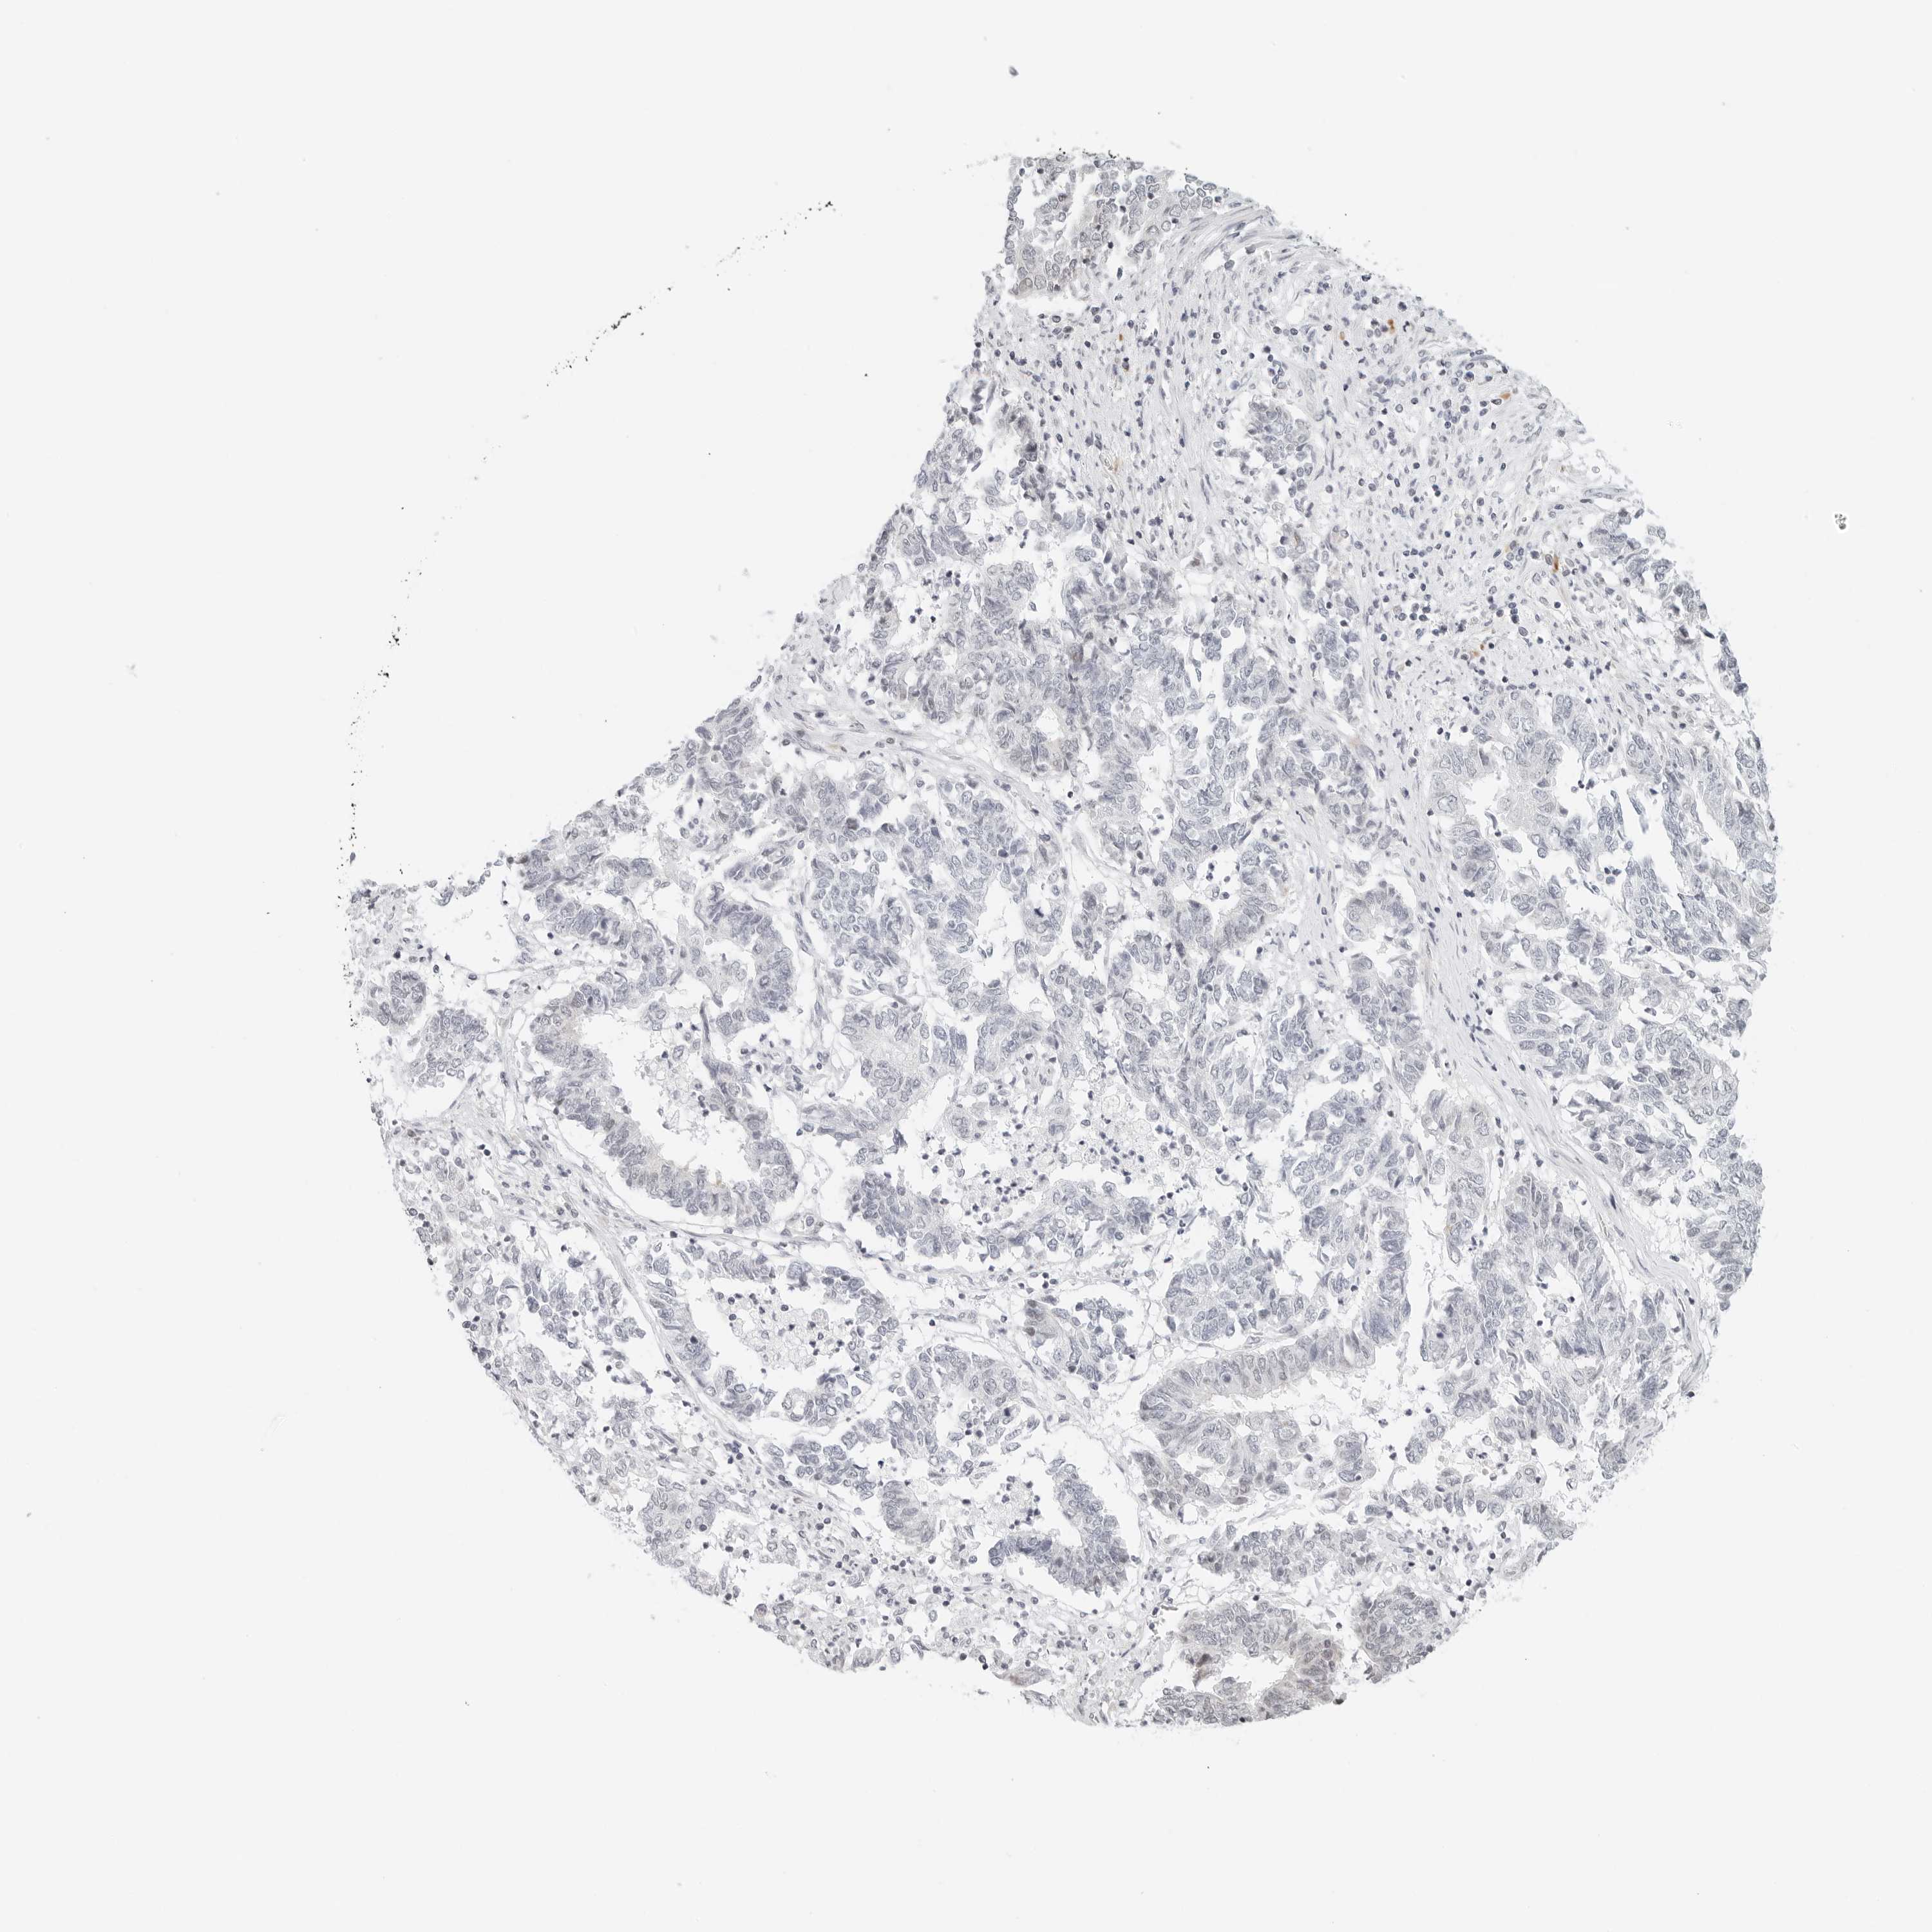

ENDOMETRIAL CANCER - Protein expressioni

A mouse-over function shows sample information and annotation data. Click on an image to view it in a full screen mode. Samples can be filtered based on level of antibody staining by selecting one or several of the following categories: high, medium, low and not detected. The assay and annotation is described here.

Note that samples used for immunohistochemistry by the Human Protein Atlas do not correspond to samples in the TCGA dataset.

Antibody stainingi

Antibody staining in the annotated cell types in the current human tissue is reported as not detected, low, medium, or high, based on conventional immunohistochemistry profiling in selected tissues. This score is based on the combination of the staining intensity and fraction of stained cells.

Each image is clickable and will lead to virtual microscopy that enables deeper exploration of all samples and also displays staining intensity scores, fraction scores and subcellular localization as well as patient and tissue information for each sample.

Antibody HPA028122

Staining

High

Medium

Low

Not detected

Intensity

Strong

Moderate

Weak

Negative

Quantity

>75%

75%-25%

<25%

None

Location

Nuclear

Cytoplasmic/membranous

Cytoplasmic/membranous,nuclear

Adenocarcinoma, NOS

Adenocarcinoma, metastatic, NOS